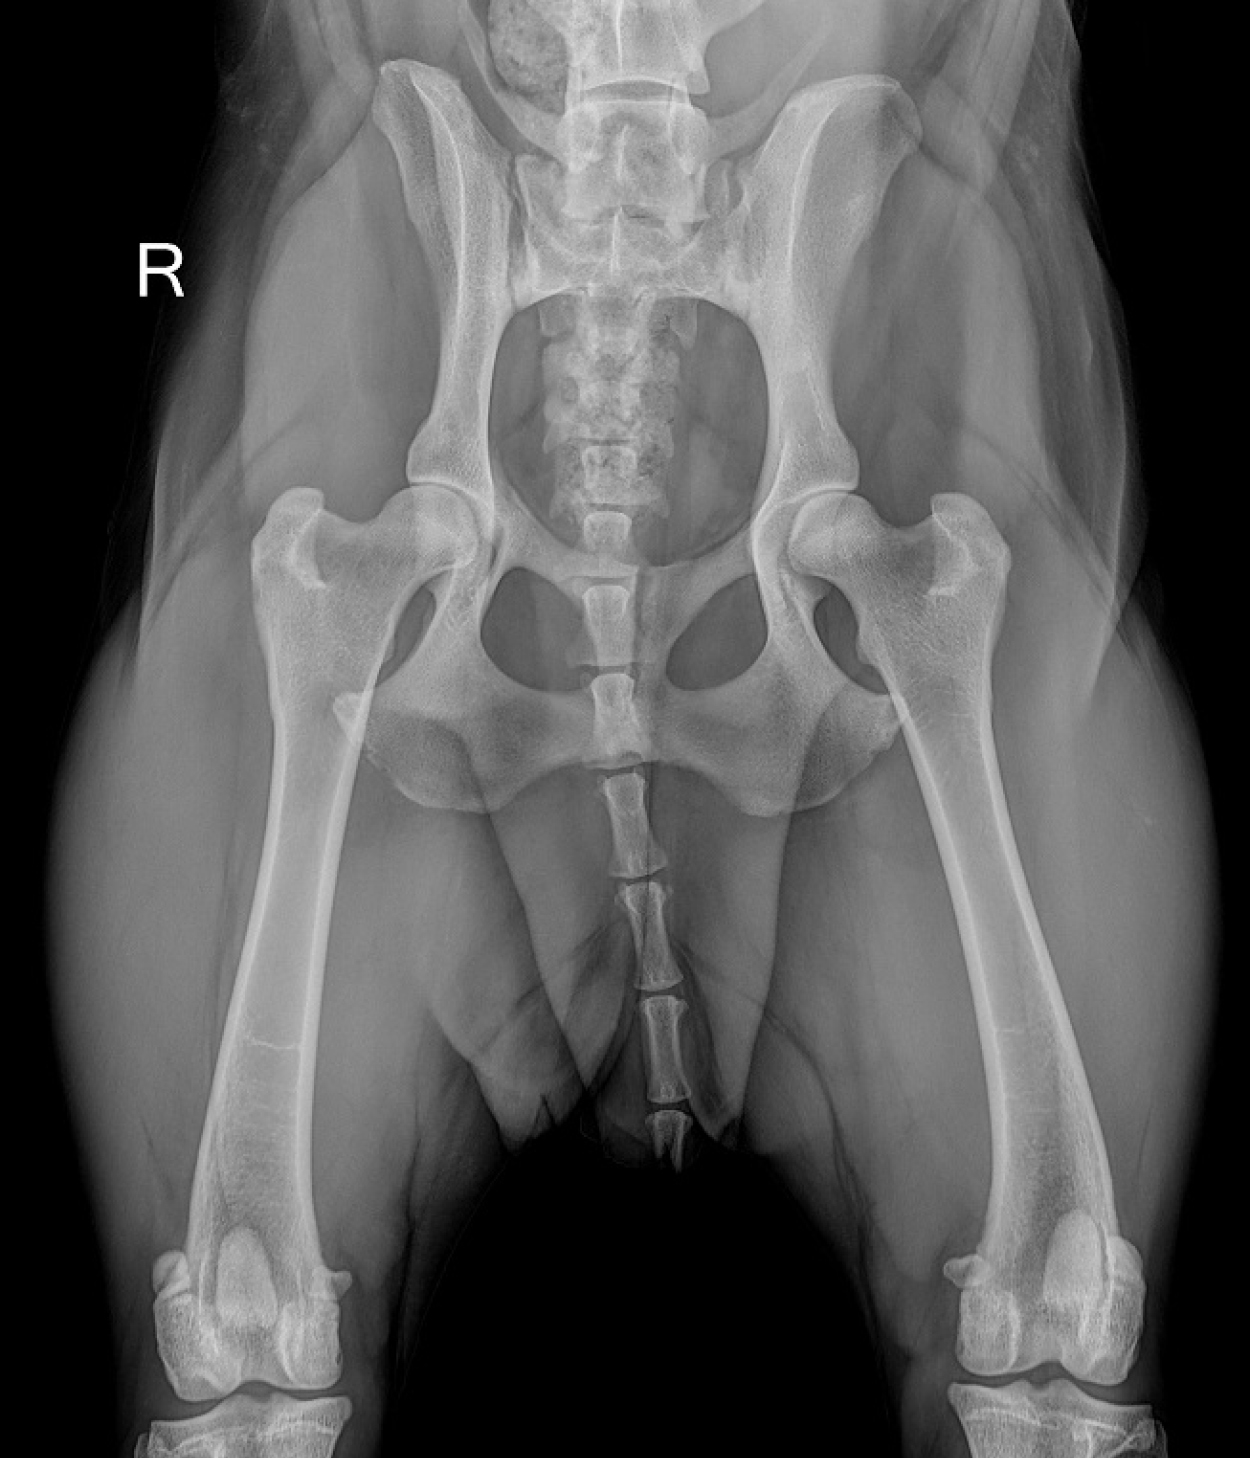

In unserem Kleintiercentrum Köllertal haben wir schon lange auf digitales Röntgen umgestellt und unsere Röntgenanlage selbst noch mal modernisiert. Wir haben das digitale Röntgensystem von XDR1 auf das moderne und hochauflösende  XDR4 umgestellt.

Somit können wir eine „4K Auflösung“ und somit höchste Qualität unserer Röntgenbilder bieten.

Bei allen Erkrankungen des Skelettsystems ist die Röntgenuntersuchung Mittel der Wahl. Brüche, Entzündungen oder degenerative Veränderungen der Knochen lassen sich mit keinem anderen Verfahren derart genau darstellen. Chirugische Eingriffe können am Röntgenbild geplant und vermessen werden.